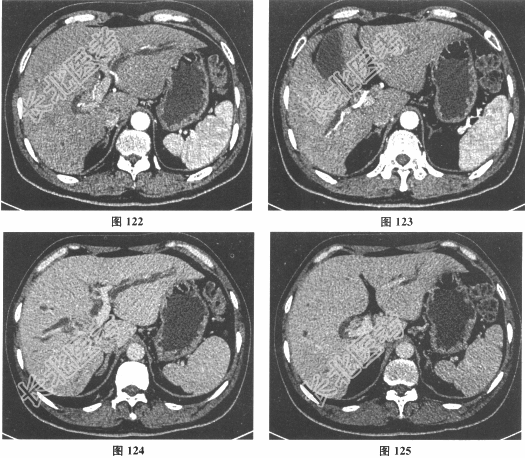

- [材料题] 患者男性,57岁,主诉"反复发热、右上腹痛2个月,巩膜皮肤黄染1周"入院。患者于2个月前无明显诱因突然出现发热、右上腹胀痛,当地医院就诊,给予抗炎对症治疗后缓解。之后发热、右上腹胀痛反复发作,外院行腹部CT检查示:"高位胆道梗阻,伴肝内胆管扩张"。1周前患者出现巩膜皮肤黄染。病来体重无明显变化,大便灰白,小便颜色加深。否认肝炎、结核病史。入院查CA19-9 1890U/ml,CEA2.56U/ml,AFP2.3ng/ml,CA12513.3U/ml,MRI和CT结果见图120~图125。

- 多项选择题1.该患者的临床诊断考虑为( )

- 多项选择题2.该患者的Bismuth-Corlette分型为( )

- 多项选择题3.该患者按"国际胆管癌协会分期系统"的分型是( )